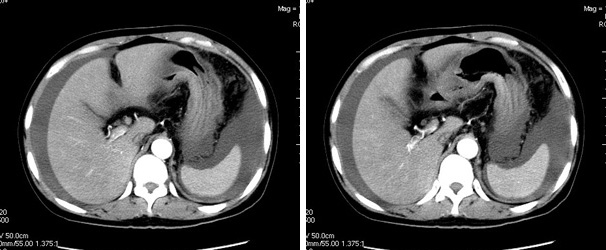

增强

真是少见!至少本人从未见过!整个消化道除了胃壁以外整套小肠及结肠肠壁均不同程度增厚水肿,肠壁间未见积气,亦未见明显的血运障碍(肠细膜上动静脉均显示很好)。盆腹腔积液。

真是少见!至少本人从未见过!整个消化道除了胃壁以外整套小肠及结肠肠壁均不同程度增厚水肿,增强明显分层[粘膜层及浆膜层明显强化,粘膜下层强化轻]。结合病史考虑肠道缺血改变[病因待查--血管炎,结缔组织疾病等]

楼主上传图像很漂亮。把每幅图像放大,增强扫描,发现肠系膜上静脉管腔变形,其内见半圆形等密度影,结合病史,考虑肠系膜上静脉栓塞并肠壁间水肿,腹水。(这是首次发的话题)

真是少见!至少本人从未见过!整个消化道除了胃壁以外整套小肠及结肠肠壁均不同程度环形增厚,肠壁密度均匀呈“晕圈”样改变,粘膜下层低密度,粘膜层和外层为相对高密度。增强强化不明显。结合病史考虑肠道急性缺血改变。腹水。形成原因肠系膜动脉栓塞、还是静脉血栓形成看不懂。

我们仔细看了三期增强的动静脉血管,未看见血栓的形成,因为三期的片子太多有168张,无法全部上传,在动脉期及静脉期看到下腔静脉及门静脉内密度不均匀在平衡期均显示均匀,所以不考虑血栓形成引起的回流障碍.刚才老公在电脑边走过(他是外行),发表意见说这人是不是吃了什么东西引起肠子中毒.我想了一下似乎有道理,但是是什么东西会引起这样的改变,并且从病程上来看有一个多月的病史,又不是急性发作,网上高手们给予指点,如需要更多的另两期的图片,我将上传.

肝周、脾脏周围可见腹水,盆腔可见积液;肠管壁广泛的增厚,密度减低,可见液体积聚在粘膜下层里面,首先还是考虑血管引起的。感染放在后面吧。

肠管壁增厚,以升结肠、横结肠明显,肠袋变浅,cta显示肠系膜上动、静脉显影清楚,管腔未见狭窄,同时大量腹水,考虑:肠麻痹水肿?食物中毒?

本例ct表现是肠道的整体性充血、水肿,以结肠特别是横结肠、升结肠、盲肠为显著,横结肠一眼粗略看过去,极似极度水肿之胰腺。回肠末段亦呈明显近似结肠改变,小肠则以充血为主,水肿相对轻微。诸段肠管无明显如溃疡、出血等局部损害,重度腹水。肝脏体积变小,肝裂增宽,以肝圆韧带为明显。肝脏各部比例尚正常,无局部外突或内凹,密度均匀一致。胆囊增大,所给图片及楼主已经仔细观察过,肝段下腔静脉肠系膜静脉均正常。